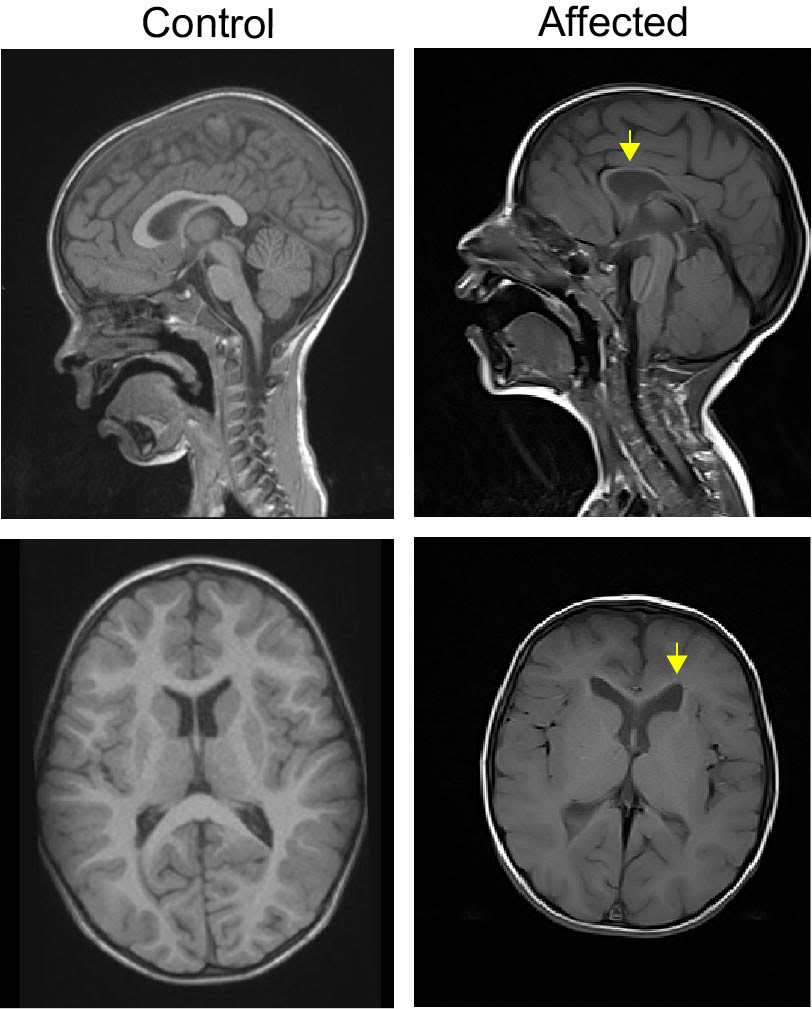

The overlapping and non-specific symptoms observed in patients with intellectual disability syndromes can make diagnosis difficult. Here, we report a new genetic intellectual disability syndrome in 8 patients characterized by moderate to severe intellectual disability, delayed verbal and motor milestones, and hypotonia. All patients have pathogenic variants in TTC5, a scaffold protein linked to many cellular processes; most notably DNA acetylation. Brain imaging revealed structural brain defects including a thin corpus callosum and cerebral atrophy with dilated lateral ventricles and simplified gyral pattern. These cornerstone clinical features can be used to prioritize this syndrome for diagnosis. (https://jmg.bmj.com/content/early/2020/05/21/jmedgenet-2020-106849 )

Bi-allelic TTC5 variants cause delayed developmental milestones and intellectual disability (Contributed by Dr. Ashleigh E Schaffer)